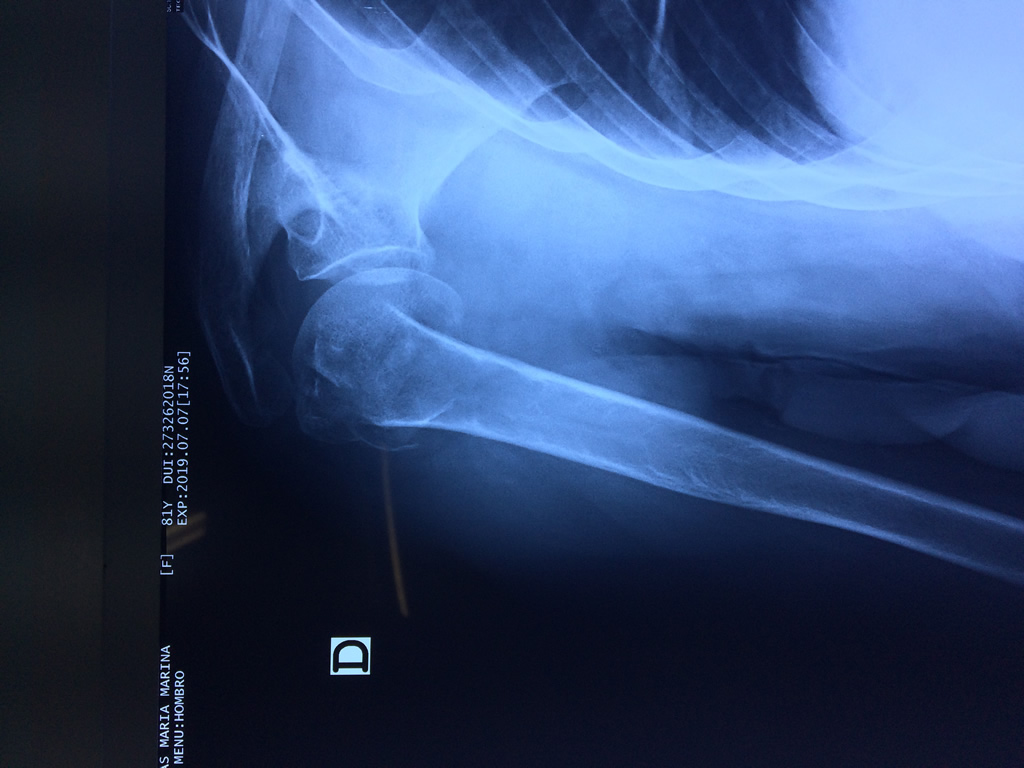

En anatomía humana, el hombro es la parte del cuerpo donde se une el brazo con el tronco. Está formado por la conjunción de los extremos de tres huesos: la clavícula, la escápula y el húmero; así como por músculos, ligamentos y tendones.

La principal articulación del hombro es la que une la cabeza del húmero con la escápula, recibe el nombre de articulación escapulohumeral y presenta dos superficies articulares, una de ellas corresponde a la cabeza del humero que tiene forma semiesférica y la otra es la cavidad glenoidea de la escápula, estas superficies están recubiertos por cartílago que permiten un movimiento suave e indoloro.

Exteriormente una envoltura de tejido blando circunda el conjunto, es la llamada cápsula articular que está reforzada por varios ligamentos que le dan estabilidad e impiden que los huesos se desplacen más allá de sus límites fisiológicos. Un conjunto de músculos y sus tendones se unen a las superficies de los huesos y hacen posible la movilidad de la articulación, entre ellos es muy importante el manguito rotador formado por cuatro músculos que proporcionan movilidad y estabilidad al hombro.

Varias estructuras transparentes en forma de saco llamadas bolsas serosas, permiten el deslizamiento suave de los diferentes componentes móviles. El hombro es la articulación con mayor amplitud de movimientos del cuerpo humano.